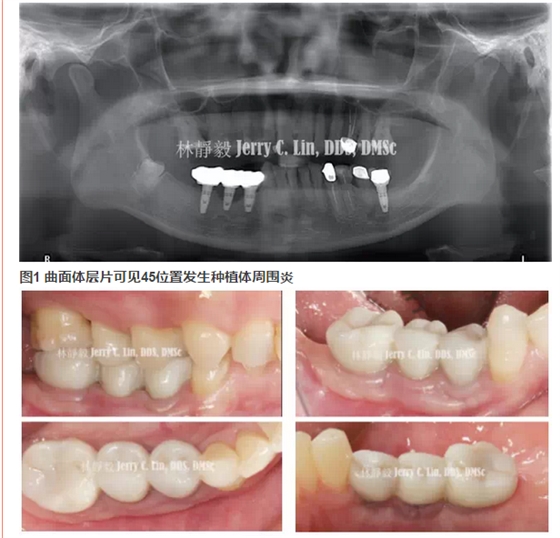

【口腔種植】嚴重種植體周圍炎的處理(二)——林靜毅醫(yī)師